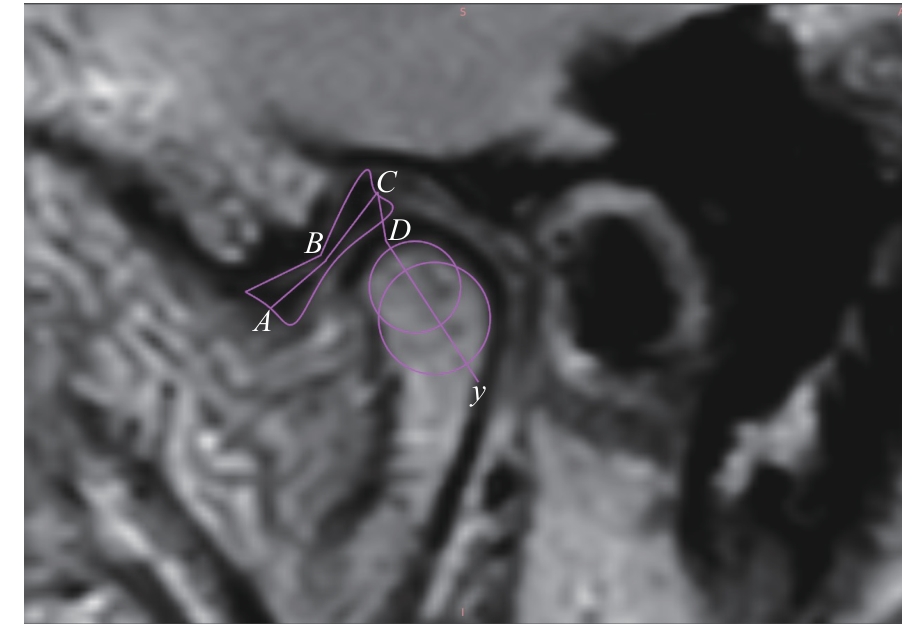

| 图4 盘髁距离及关节盘长度的测量 Note: An oblique sagittal PDWI image. A—the midpoint of the anterior edge of the anterior band of the articular disc; B—the midpoint of the intermediate zone of the articular disc; C—the midpoint of the posterior edge of the posterior band of the articular disc; y—the long axis of the condylar head; D—the intersection of y-axis with the condyle; AB+BC—the length of the articular disc; CD—the disc-condyle distance. |

| Fig 4 Measurement of disc-condyle distance and articular disc length |